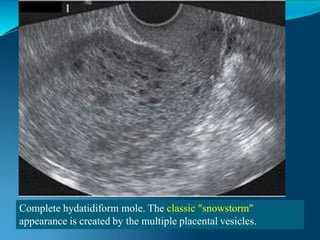

Complete Molar Pregnancy

Complete hydatidiform mole. The classic "snowstorm"

appearance is created by the multiple placental vesicles.